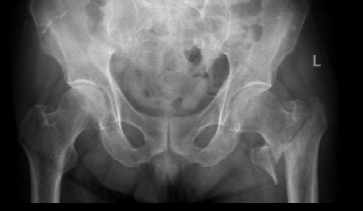

患者张爷爷已逾九旬,基础疾病错综复杂:前列腺癌病史3年、高血压20年、糖尿病30年,10天前因脑梗死导致左侧肢体活动不便。然而近日,厄运再次降临,他在家如厕时不慎跌倒,造成“左侧股骨转子间粉碎型骨折”,被紧急送至我院。

入院时,老人情况十分危急:除骨折外,还存在Ⅰ型呼吸衰竭、慢性支气管炎急性加重、低钠血症及贫血。入院后其呼吸功能进一步恶化,随即被转入ICU,进行气管插管、呼吸机辅助呼吸。经过ICU团队5天昼夜不停的全力救治,张爷爷的呼吸功能终于显著改善,成功拔管,脱离了生命危险。

ICU与呼吸内科团队确保患者拔管后呼吸功能稳定;心血管内科、内分泌科精准调控血压、血糖至精准范围;神经内科评估脑梗后状态。手术麻醉科量身定制创伤最小、最稳定的个性化麻醉与监测方案,严阵以待可能出现的循环呼吸波动。在此基础上,骨科团队最终决定采用微创的“闭合复位髓内钉内固定术”,力求以最短时间、最小创伤完成固定。

在万全准备下,手术如期展开。术中,多学科团队配合默契,操作精准流畅。仅用时40分钟便成功完成骨折复位与固定,术中出血极少,患者生命体征平稳。这场高风险手术取得了关键性胜利。